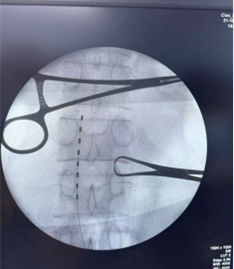

在术中电生理和术中影像的引导下,通过穿刺的技术将1根穿刺电极精准放置在偏瘫侧胸12到腰1位置。术中电生理测试良好。

术中测试电极部位